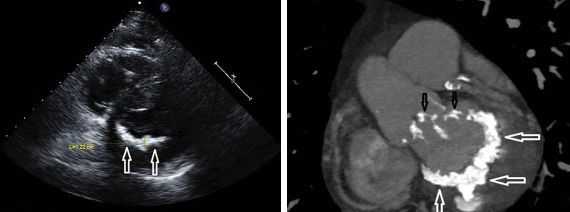

Другой важный инструментальный метод диагностики — эхокардиография (Эхо-КГ) . Эхо-КГ — это безболезненное ультразвуковое исследование, которое позволяет исследовать работу сердца в реальном времени. Эхокардиография покажет уменьшение эластичности клапана, его повреждение, размер отверстия митрального клапана и расстояние между его створками. Также при исследовании можно увидеть разрыв папиллярной мышцы и провисание клапанных створок в полость левого предсердия [4] [8] [9] .

Диастолическую функцию оценивали методом импульсной доплер-эхокардиографии по стандартной методике аппаратом «SIM 5000 plus» (Япония). Определяли следующие показатели: максимальную скорость потока периода позднего наполнения (А, см/с), максимальную скорость раннего наполнения (Е, см/с), соотношение Е/А - отношение между амплитудами волн Е и А, время изоволюмического расслабления (IVRT, мс) - период от закрытия аортального клапана до открытия митрального клапана, и DТ (с) - время замедления потока раннего наполнения. Статистическая обработка полученных данных проведена на персональном компьютере методами вариационной статистики с использованием пакетом программ «Microsoft Excel», «Statistic» с помощью критерия Стьюдента (t). Данные представлены в виде М ± m. Отличия считали достоверными при < 0,05.